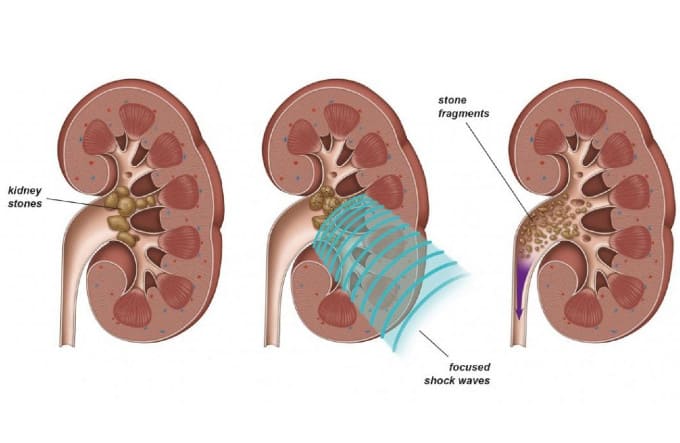

Εξωσωματική Λιθοτριψία κρουστικών κυμάτων (SWL)

Αυτή η διαδικασία (Εικ. 4&5), περιλαμβάνει τη χρήση ηχητικών κυμάτων από το εξωτερικό του σώματος για να διαλύσει ένα λίθο σε μικρότερα κομμάτια, τα οποία μπορούν στη συνέχεια να αποβληθούν φυσιολογικά με την ούρηση.

Η διαδικασία διαρκεί περίπου μία ώρα και είναι μετρίως επώδυνη. Για τον λόγο αυτό, χορηγείται φαρμακευτική παυσίπονη αγωγή. Λιγότερο συχνά, η διαδικασία της εξωσωματικής λιθοτριψίας γίνεται με νευρολήπτων αναισθησία (μέθη) με την παρουσία αναισθησιολόγου. Εάν πρόκειται για μια μεγάλη πέτρα, μπορεί να χρειαστούν αρκετές συνεδρίες για να θρυμματιστεί πλήρως.

Η λιθοτριψία κρουστικών κυμάτων δεν συνιστάται εάν:

- Είστε έγκυος

- Έχετε υψηλό κίνδυνο σοβαρής αιμορραγίας

- Έχετε οποιαδήποτε λοίμωξη

- Έχετε ανεξέλεγκτη υψηλή αρτηριακή πίεση

- Έχετε υψηλό δείκτη μάζας σώματος που σημαίνει ότι θα ήταν δύσκολο για τα ηχητικά κύματα να φτάσουν στην πέτρα λόγω της μεγάλης απόστασης από το δέρμα έως τον λίθο

- Έχετε ανεύρυσμα

- Έχετε απόφραξη στο ουροποιητικό σύστημα, κάτω από την πέτρα ή στην ουροδόχο κύστη

- Έχετε έναν πολύ σκληρό λίθο (λίθοι κυστίνης)

Εικ. 4: Εστιασμένα κρουστικά κύματα κατακερματίζουν λίθους σε μικρότερα θραύσματα